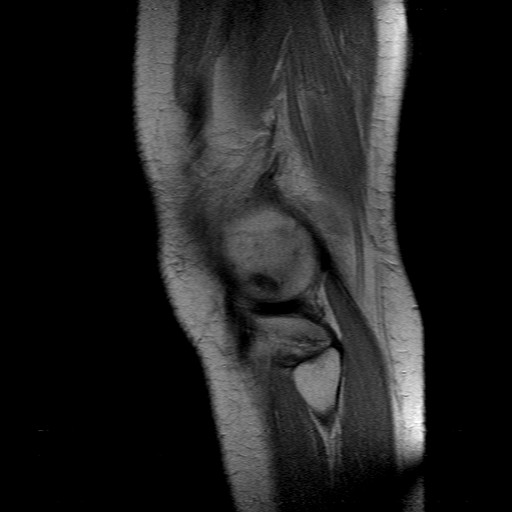

SALVE, SONO UNA DONNA DI 51 ANNI, DOPO DEI DOLORI OSSEI GENERICI IN TUTTO IL CORPO CON LA COMPARSA DI MACCHIE NELLA PELLE GONGIERI NELLA CAVIGLIA, BRUCIORE AGLI OCCHI E STANCHEZZA MI RIVOLGO DAL UN REUMATOLOGO, CHE PRESCRIVI UNA RISONZA MAGNETICA AL GINOCCHIO (DOVE HO PIÙ DOLORE), (ANCORA ASPETTO GLI ESITI DELLE ANALISI), OGGI LA RISONZA SENTENZA:

"MARCATA ALTERAZIONE DI SEGNALE, IPERINTENSA IN T2 ED ISO-IPOINTENSA IN T1, DA SEVERA SOFFERENZA DELLA SPONGIOSA OSSEA SUB CONDRALE, SI APPREZZA IN SEDE CONDILOIDEA LATERALE III MEDIO-ANTERIORE, E MILLIMETRICA ASPETTO ED INTENSITÀ DI SEGNALE DI ENTRMBE LE FIBROCARTILAGINE MENISCALE."

DA QUI LO SPECIALISTA MI DICE CHE HO UN INFARTO CONDILO FEMORALE ESTERNO AL GINOCCHIO SINISTRO, MI CONSIGLIA UN TRATTAMENTO RIABILITATIVO CON 10 SEDUTE DI MAGNETOTERAPIA E 2 MESI DI ASSOLUTO RIPOSO E CAMMINARE SOLO CON LE STAMPELLE. LE MACCHIE ED I GONFIORI NON SONO PIÙ PRESENTI MA MI È RIMASTO UN DOLORE ATROCE AL GINOCCHIO. ACCETTO TUTTI I VOSTRI CONSIGLI.. ANCHE PERCHÈ SONO DISPERATA NON CAMMINO PIÙ. GRAZIE MILLE.